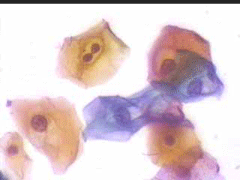

6.9.2002 Μετά από πάροδο διετίας επανέρχεται για προληπτικό έλεγχο.. Στο ιστορικό μικρο-υποτροπές κολπίτιδας, που ξεπερνούσε παροδικά με 3ήμερη χρήση Daktarin vag. supp. Το κολποσκοπικο εύρημα ήταν φυσιολογικό, ωστόσο το κυτταρολογικό επίχρισμα εμφάνιζε την τυπική πολυμορφία ερπητικών αλλοιώσεων.

4.8.2005 σε 2-3 οπτικά πεδία κυτταρολογικές ατυπίες που συνηγορούν για ερπητικές αλλοιώσεις ..

Στις 27.4.2010 εκ νέου σποραδική διακριτική κοιλοκυτταρική ατυπία και χαρακτηριστικές ατυπίες πυρηνων, που συνηγορούν, σε συνάρτηση με το ιστορικό, για ερπητικές αλλοιώσεις.